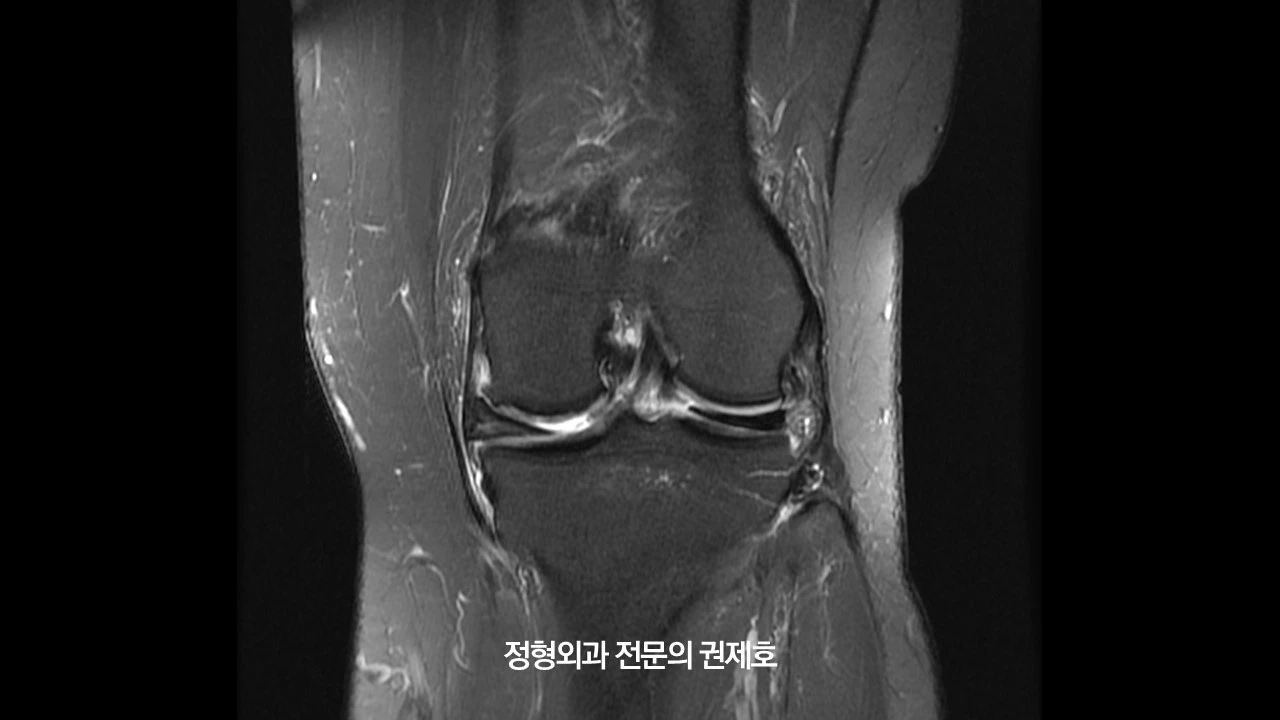

오른쪽 무릎 MRI입니다. 보시면 바깥쪽에 선천성 원판형 연골판이 존재하면서 안쪽에는 연골 손상과 함께 반월상 연골판 파열도 관찰되었습니다.

왼쪽 무릎 MRI를 보시게 되면 내측 반월상 연골판 골기시부 파열이 있으면서 오른쪽과 마찬가지고 연골 손상이 동반된 것을 아실 수 있습니다.